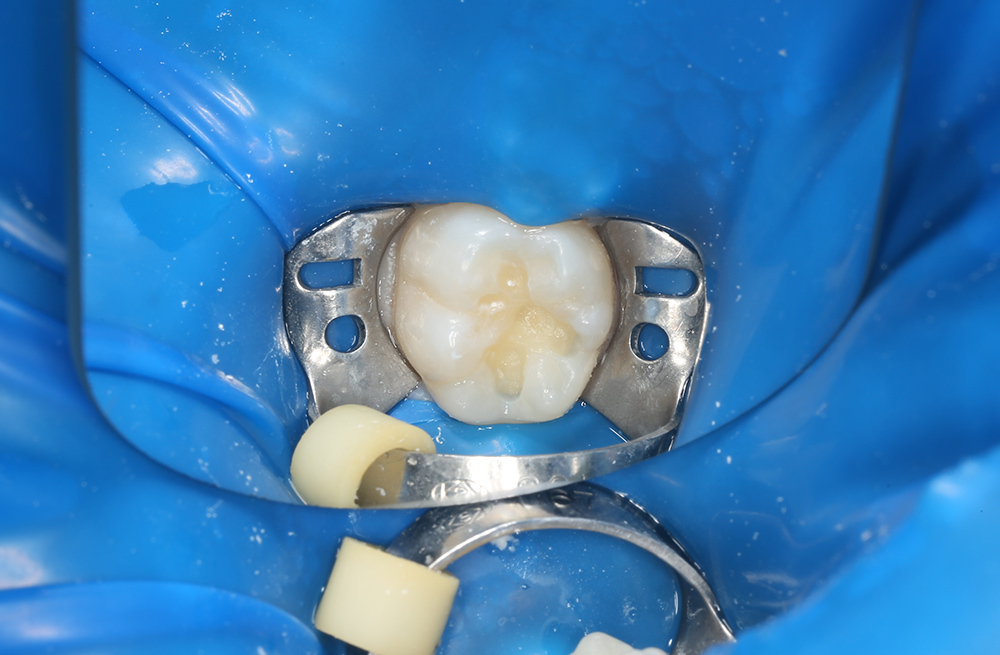

Лечение кариеса на жевательной поверхности постоянного зуба у подростка